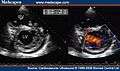

Images

Transthoracic two-dimensional echocardiogram in apical four chamber and parasternal short axis at the level of both ventricles demonstrate dilatation, deep trabeculae and intertrabecular recesses in the inferior, lateral, anterior walls, middle and apical portions of the septum and apex of the left ventricle.